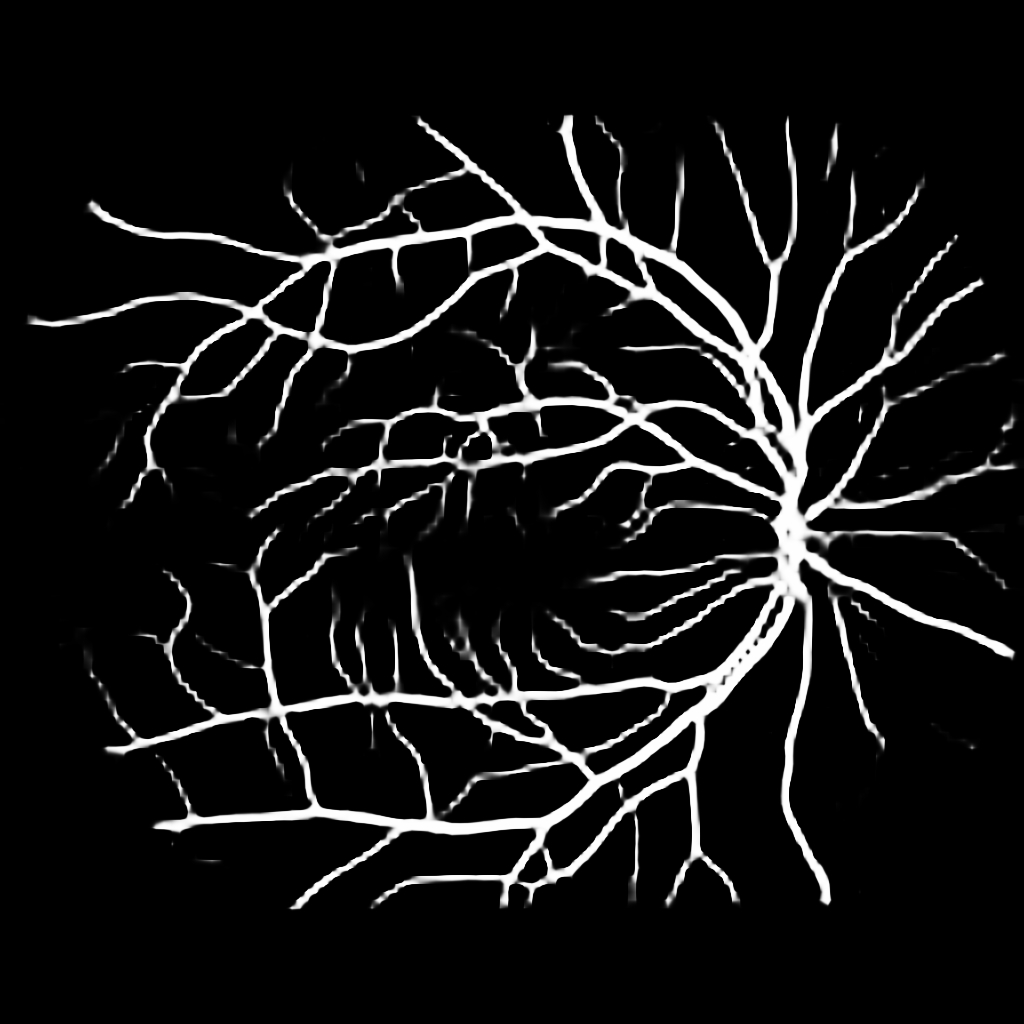

For completeness, and to test the robustness of our method, the models were also tested with several images sourced from Google™. We purposefully sourced extremely poor quality images (i.e. images with low contrast, speckle artefacts, etc), as well as images of pathological cases (i.e. Exdudates, Hemorrhages, etc). As there are no ground truth labels, only a qualitative assessment can be made of the results shown in Figure 2. In all cases, the models have accurately segmented the vessel structure whilst ignoring imaging artifacts and pathological lesions. This is very evident in the case of (5) and (6) where no vessels were segmented in areas of severe hemorrhaging.

{L to R: (1) Healthy, (2) Unhealthy, (3) Speckle Artefacts, (4) NPDR, (5) PDR, (6) Hemorrhages}